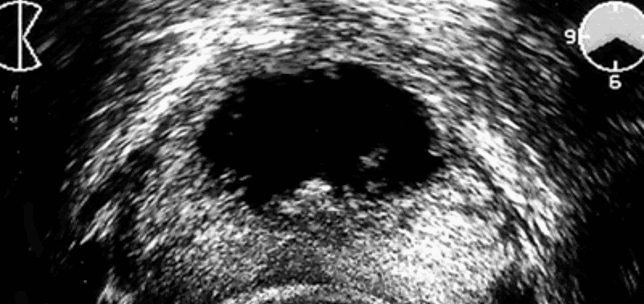

Rotterdam Prostate Cancer Risk app